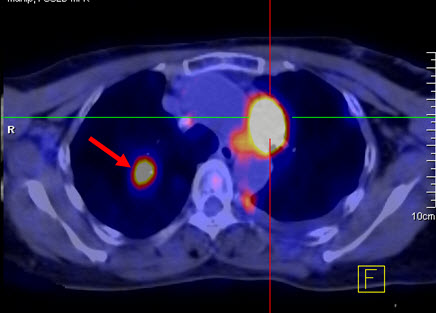

Hình 2a: Hình PET toàn thân của bệnh nhân Đỗ Thị N., 87 tuổi. thấy khối u ở vú phải (mũi tên đỏ) và hai hạch nách phải (mũi tên xanh) tăng hấp thu FDG.

Hình 2b: cho thấy rõ mức độ tập trung cao FDG tại vùng có khối u ở vú phải, max SUV=10,24.

Hình 2c: cho thấy hình ảnh hai hạch nách tăng hấp thu FDG (hạch di căn ung thư vú).